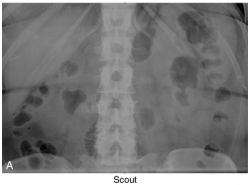

48.雙側輸尿管阻塞常會造成腎臟功能及電解質之不平衡, 請問下列敘述何者正確? (A) 比起單側輸尿管阻塞,雙側輸尿管阻塞較不容易出現 Postobstructive diuresis (B) 在雙側輸尿管阻塞 24 小時後,Aquaporin 2 (AQP2) 的表現會顯著增加 (C) 即使解決雙側輸尿管阻塞 30 天後,Aquaporin 2 (AQP2) 的表現仍然會持續降 低, 造成長期多尿及影響濃縮尿液之功能 (D) 比起單側輸尿管阻塞,雙側輸尿管阻塞更容易造成鈉,水分及尿素氮之滯留, 並增加 atrial natriuretic peptide 之製造 (E) 輸尿管阻塞會顯著的降低腎臟 acid-base transporters 之功能,包括 type 1 Na+/H+ exchanger,